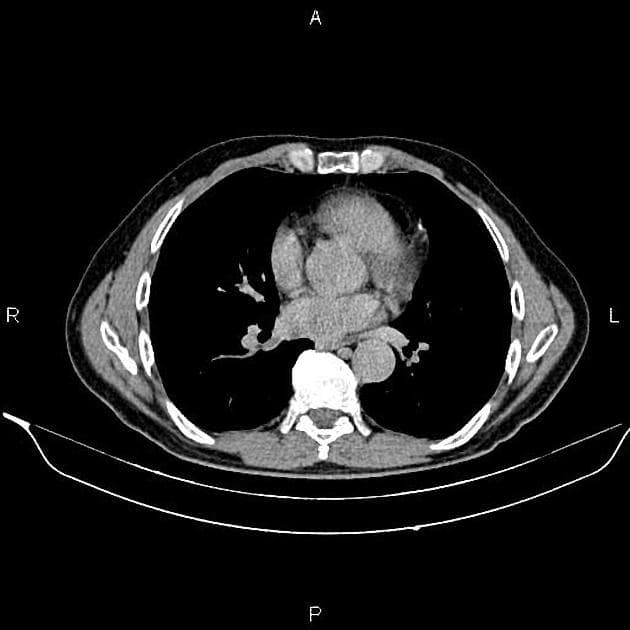

- Một khối nang khu trú một phần lồi ra ngoài (exophytic) kích thước 48 mm, thành dày ngấm thuốc (enhancement) và có các vách ngăn cùng các nốt ngấm thuốc lệch tâm (eccentric enhancing nodules) được ghi nhận ở phần giữa của thận phải.

- Một vài mạch máu tuần hoàn bàng hệ (collateral circulation) nhỏ giãn được ghi nhận trong khoảng gian thận (perinephric space).

Khối nang thận - phân loại Bosniak IV (Renal cystic mass - Bosniak class IV)

- "Các khối nang thận phân loại Bosniak IV có nguy cơ ác tính từ 70-90% và thường là ung thư biểu mô tế bào thận dạng nang."

- "Các đặc điểm hình ảnh chính bao gồm thành dày ngấm thuốc, vách ngăn ngấm thuốc và các nốt ngấm thuốc lệch tâm."